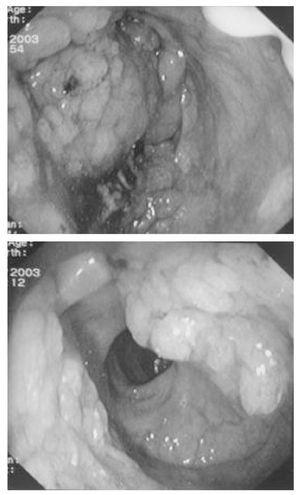

Figura. 1. Imágenes obtenidas durante la colonoscopia que muestran una formación polipoidea sésil en la ampolla rectal.

Mujer de 74 años que, tras presentar durante 5 días dolor abdominal y vómitos, ingresa en el hospital por obnubilación y anuria. Sus antecedentes incluían obesidad, diabetes mellitus tratada con metformina (750 mg/8 horas) y glibenclamida (5 mg/8 horas). La presión arterial era de 105/60 mmHg, la frecuencia cardíaca de 155 latidos por minuto, la temperatura de 36,7 ºC y la frecuencia respiratoria de 40 respiraciones por minuto. En la exploración destacaba deshidratación intensa, desorientación, dolor abdominal con peristaltismo débil y ausencia de defensa abdominal. Los principales datos analíticos fueron: glucosa 11,9 mmol/l, creatinina 625,2 µmol/l, urea 70,7 mmol/l, amilasa 2.605 U/l, sodio 148 mmol/l, potasio 3,0 mmol/l, cloro 86,9 mmol/l, leucocitos 36 x 109/l con 86% de neutrófilos, hemoglobina 114 g/l y plaquetas 439 x 109/l. La gasometría arterial (fracción inspiratoria de oxígeno [FiO2 de 0,4]) mostró una acidosis metabólica grave (pH 6,88, presión parcial de CO2 en sangre arterial [PaCO2] 21 mmHg, PaO2 129 mmHg y bicarbonato 4,0 mmol/l). El anión gap era de 50 y el lactato sérico de 17,8 mmol/l (normal: inferior a 2,2). La radiografía de tórax fue normal y el electrocardiograma (ECG) puso de manifiesto una fibrilación auricular y alteraciones inespecíficas de la repolarización. Una tomografía computarizada (TC) abdominal descubrió un aumento del tamaño de la cabeza del páncreas. La paciente recibió tratamiento con ventilación mecánica, fluidos con suplementos de potasio, noradrenalina, bicarbonato, insulina, amiodarona, imipenen y furosemida. Al segundo día de ingreso, tras administrar de 750 mmol de bicarbonato y 140 mmol de potasio, se normalizó el equilibrio ácido-básico (pH 7,41 y bicarbonato 20 mmol/l) e hidroelectrolítico (sodio 147 mmol/l, potasio 3,5 mmol/l, cloro 95,6 mmol/l), y la creatinina descendió a 488 µmol/l. Al tercer día de ingreso, por la presencia de deposiciones mucosas repetidas, se realizó una colonoscopia que puso de manifiesto una formación polipoidea sésil situada a 2 cm del esfínter anal y de 14 cm de longitud (fig. 1). Reinterrogada la familia, se averiguó que la paciente llevaba pañales desde hacía 10 años por diarreas mucosas que habían sido malinterpretadas como incontinencia anal. La biopsia obtenida durante la coloscopia dio como resultado un adenoma velloso rectal. Al séptimo día de ingreso, la enferma fue extubada y dos días más tarde fue trasladada a planta para extirpación del adenoma velloso.